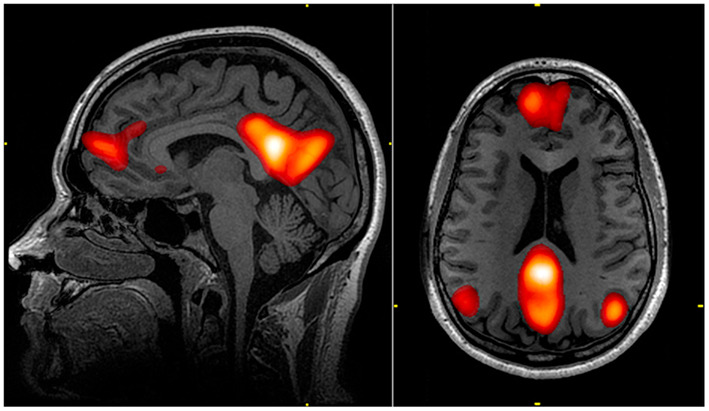

놀랍게도 우리가 의식적으로 무언가를 하지 않을 때, 뇌의 특정 영역인 '디폴트 모드 네트워크(Default Mode Network, DMN)'는 오히려 더 활성화된다고 합니다. 이 DMN은 과거의 기억을 정리하고, 미래를 계획하며, 타인의 마음을 헤아리는 등 매우 중요한 역할을 수행합니다.